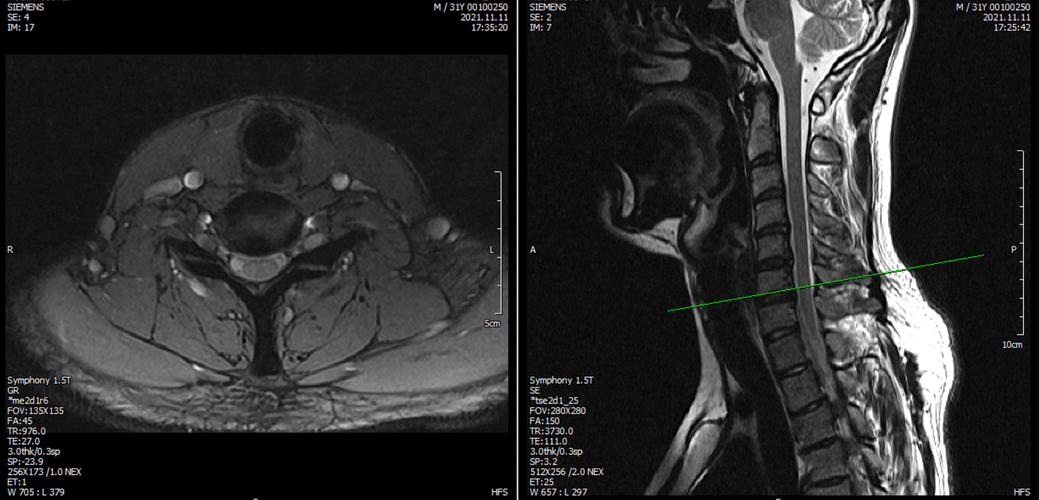

아래는 저의 경추과 요추 MRI 사진 첨부합니다.

• 1번 째 사진

• 2번 째 사진

목디스크로 인해 상하지의 힘이 다 빠지려면 척수까지 침범하는 병변이 있어야 합니다.

그런 상황이 아니므로 디스크는 배제해도 되겠습니다.